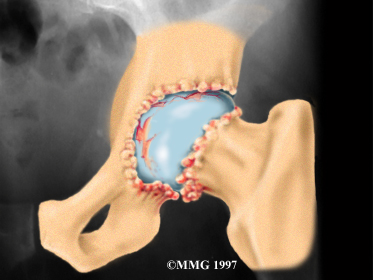

Articular cartilage is the smooth lining that covers the surfaces of the ball-and-socket joint of the hip. The cartilage gives the joint freedom of movement by decreasing friction. The layer of bone just below the articular cartilage is called subchondral bone. The main problem in OA is degeneration of the articular cartilage.

When the , or wears away, the subchondral bone is uncovered and rubs against bone. Small outgrowths called bone spurs or osteophytes may form in the joint.

The diagnosis of hip OA starts with a complete history and physical examination by your doctor. X-rays will be required to determine the extent of the cartilage damage and suggest a possible cause for it.

Your doctor will order X-rays to determine the extent of the cartilage damage and suggest a possible cause for it.